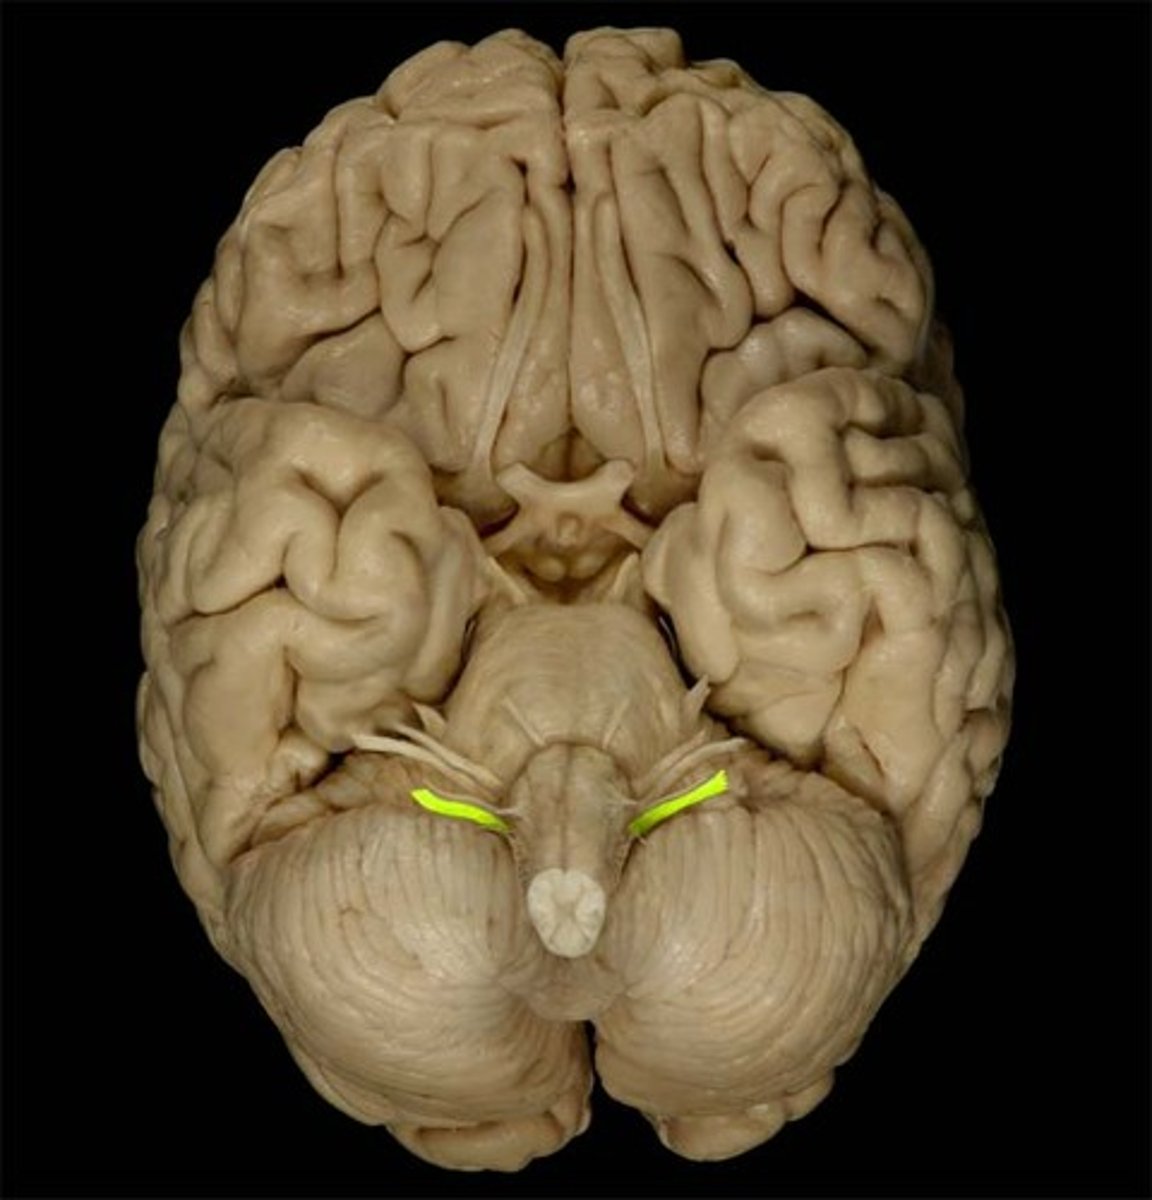

trochlear nerve (CN IV)

Motor cranial nerve that controls movement of the eye inferiorly and laterally; innervates superior oblique muscle